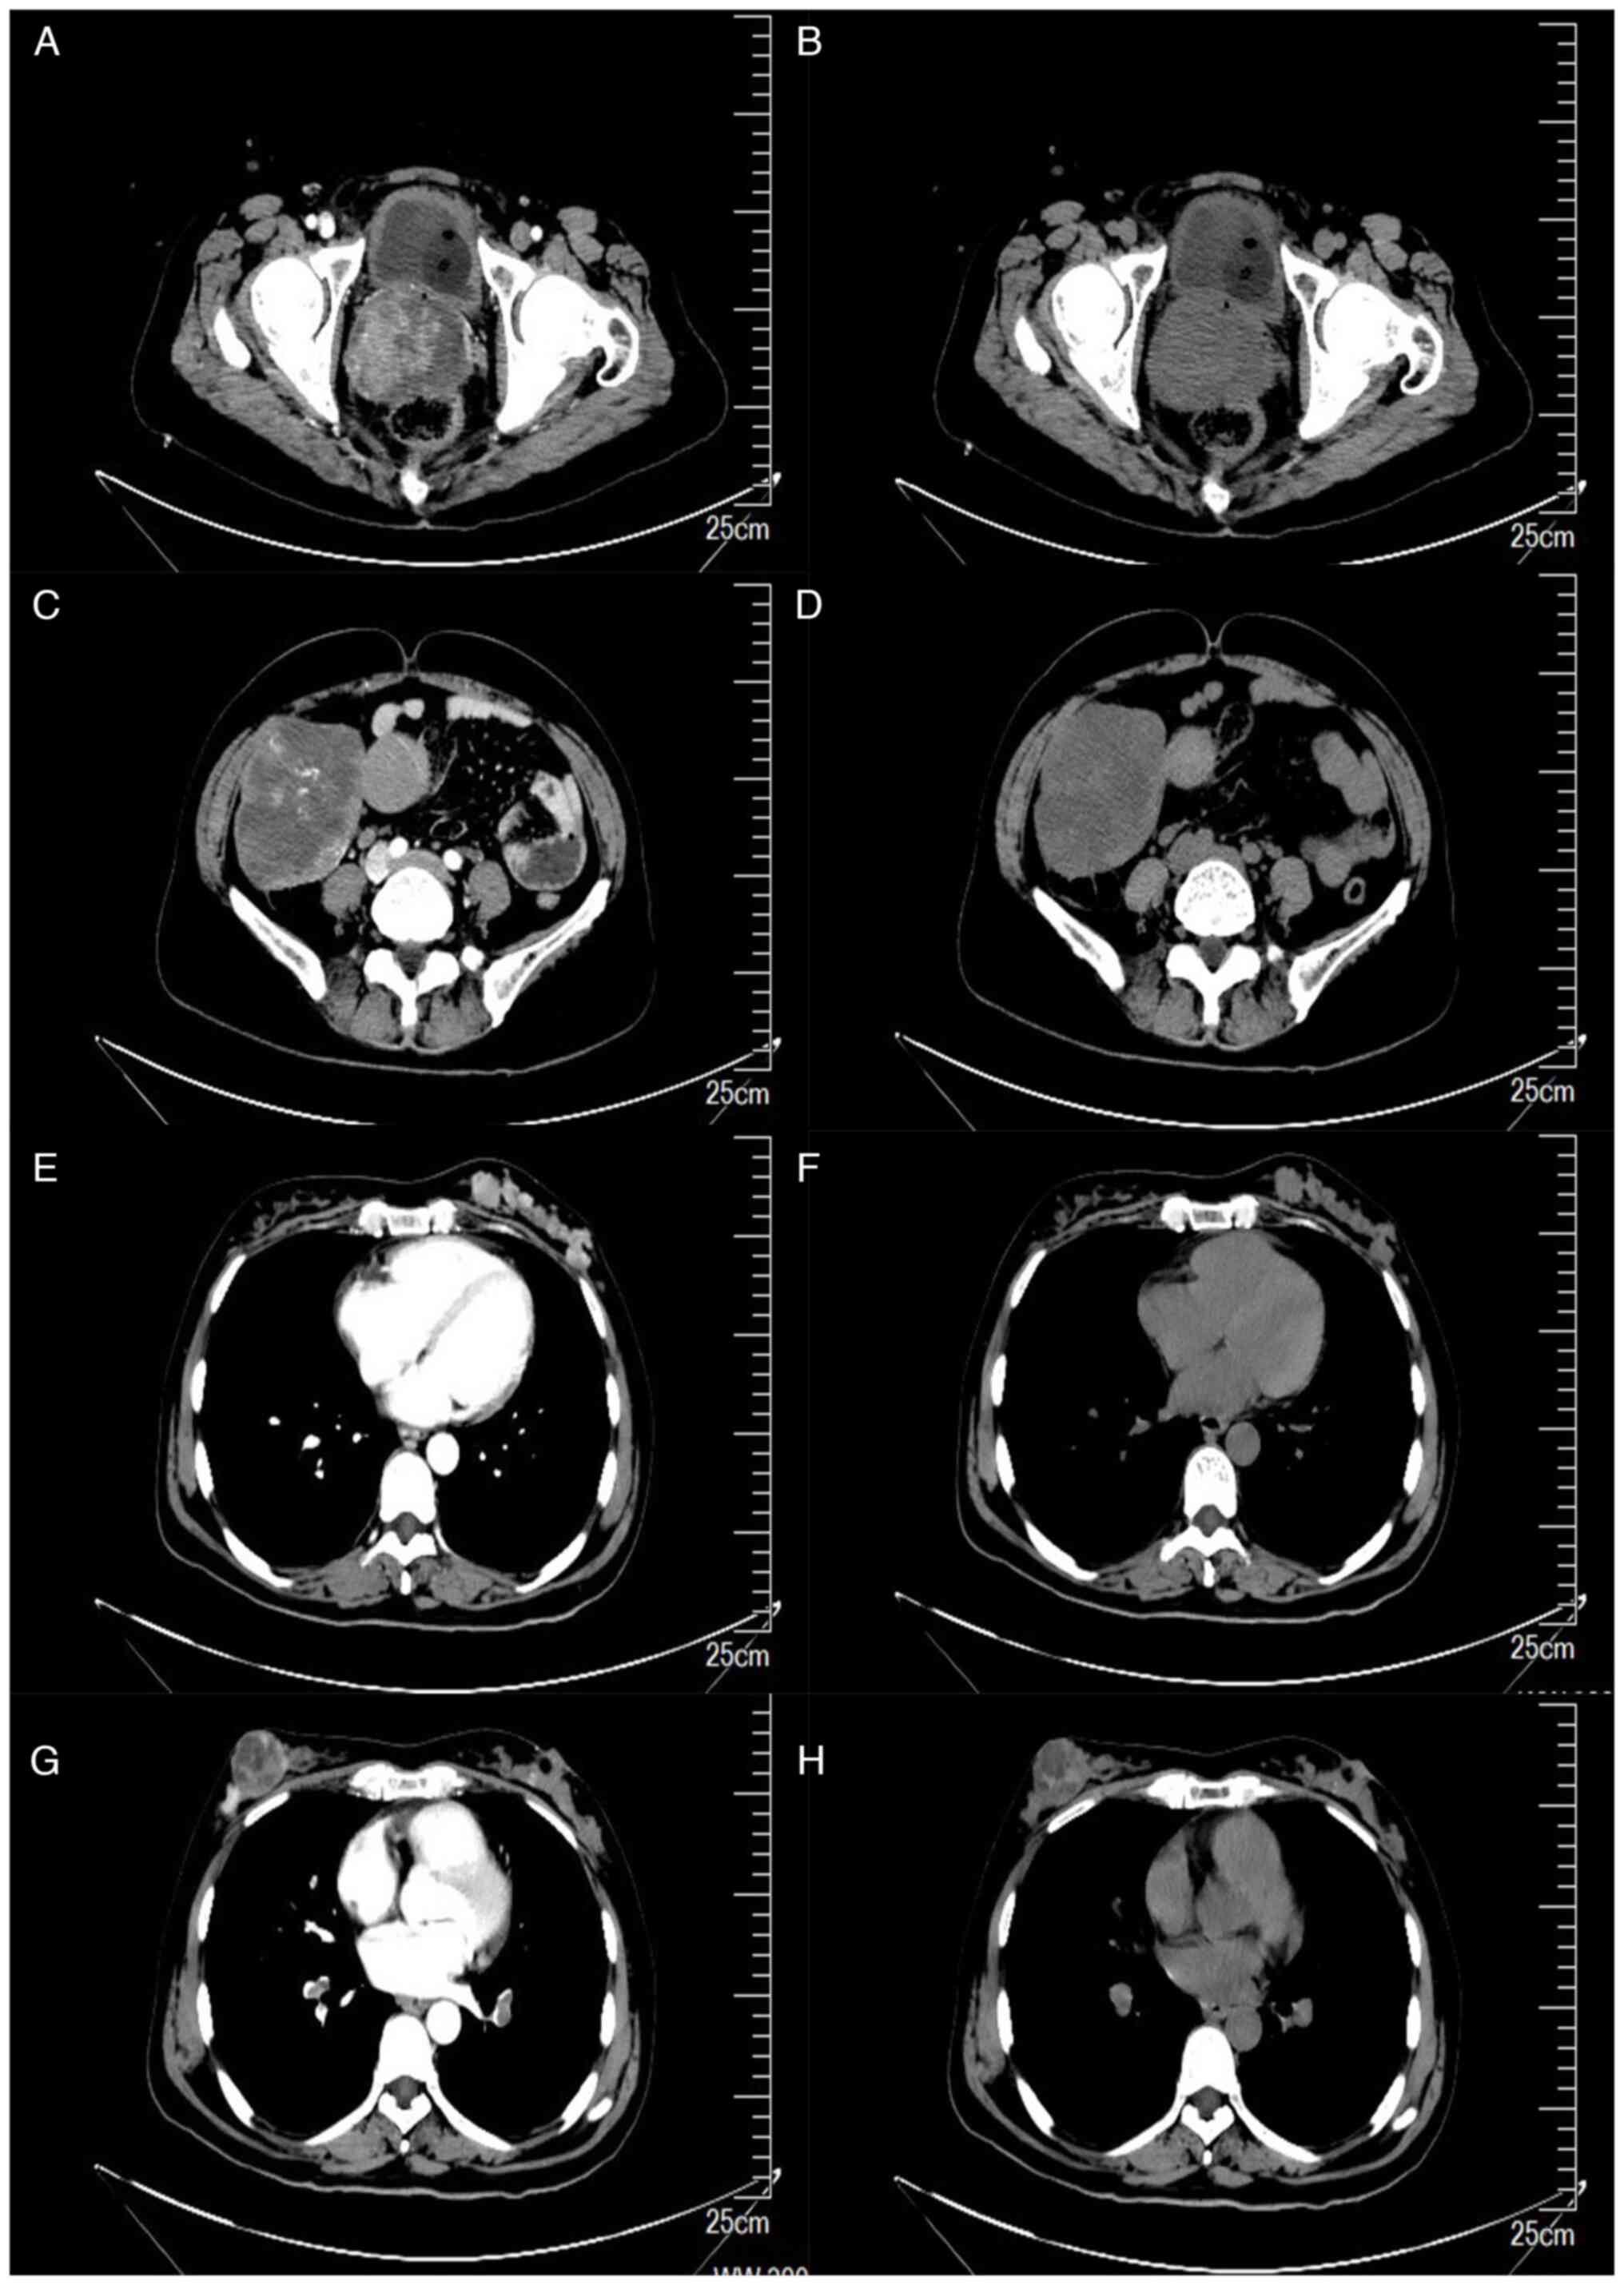

Multiple synchronous primary malignant neoplasms: A case report and literature review

Multiple primary malignant neoplasms (MPMN) are defined as two or more primary malignancies diagnosed in an individual. There is no association between these cancers, which can be classified into synchronous and heterochronous cancers depending on the time of diagnosis. The present study presented a rare case of bilateral breast, endometrial, cervical and ovarian cancers. Through thorough physical examination, pathology and immunohistochemistry, it could be determined that bilateral breast, endometrial and cervical cancers were primary malignant tumors and that ovarian cancer cannot be excluded as a result of metastasis. the present study also summarized the definitions, risk factors, prevalence characteristics, diagnostic ideas and treatment options for MPMN by reviewing the literature.